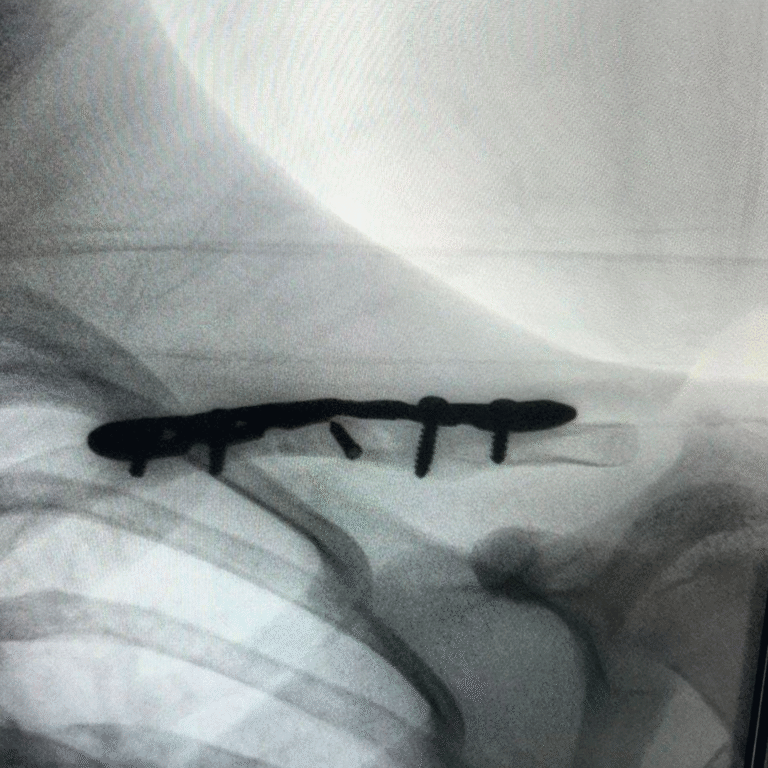

🩺 Resultados que transforman vidas. Descubre cómo hemos devuelto la movilidad y eliminado el dolor de mis pacientes mediante tratamientos efectivos.